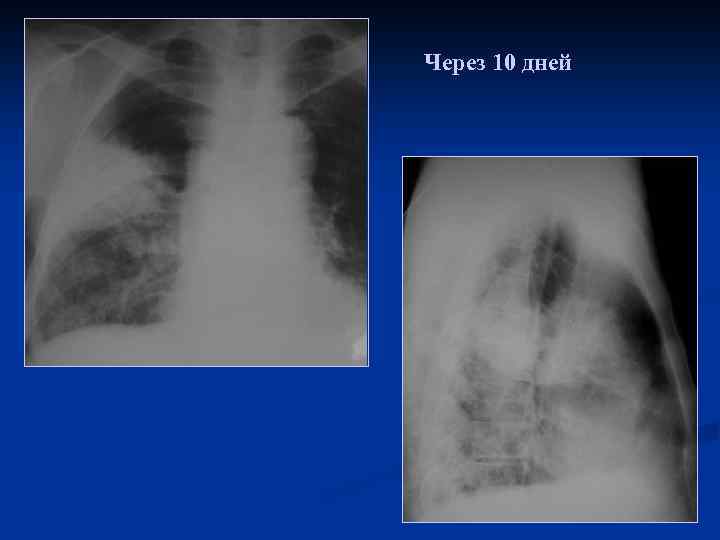

Длительное течение пневмонии, отсутствие выраженной динамики 1

Через 10 дней

2

3